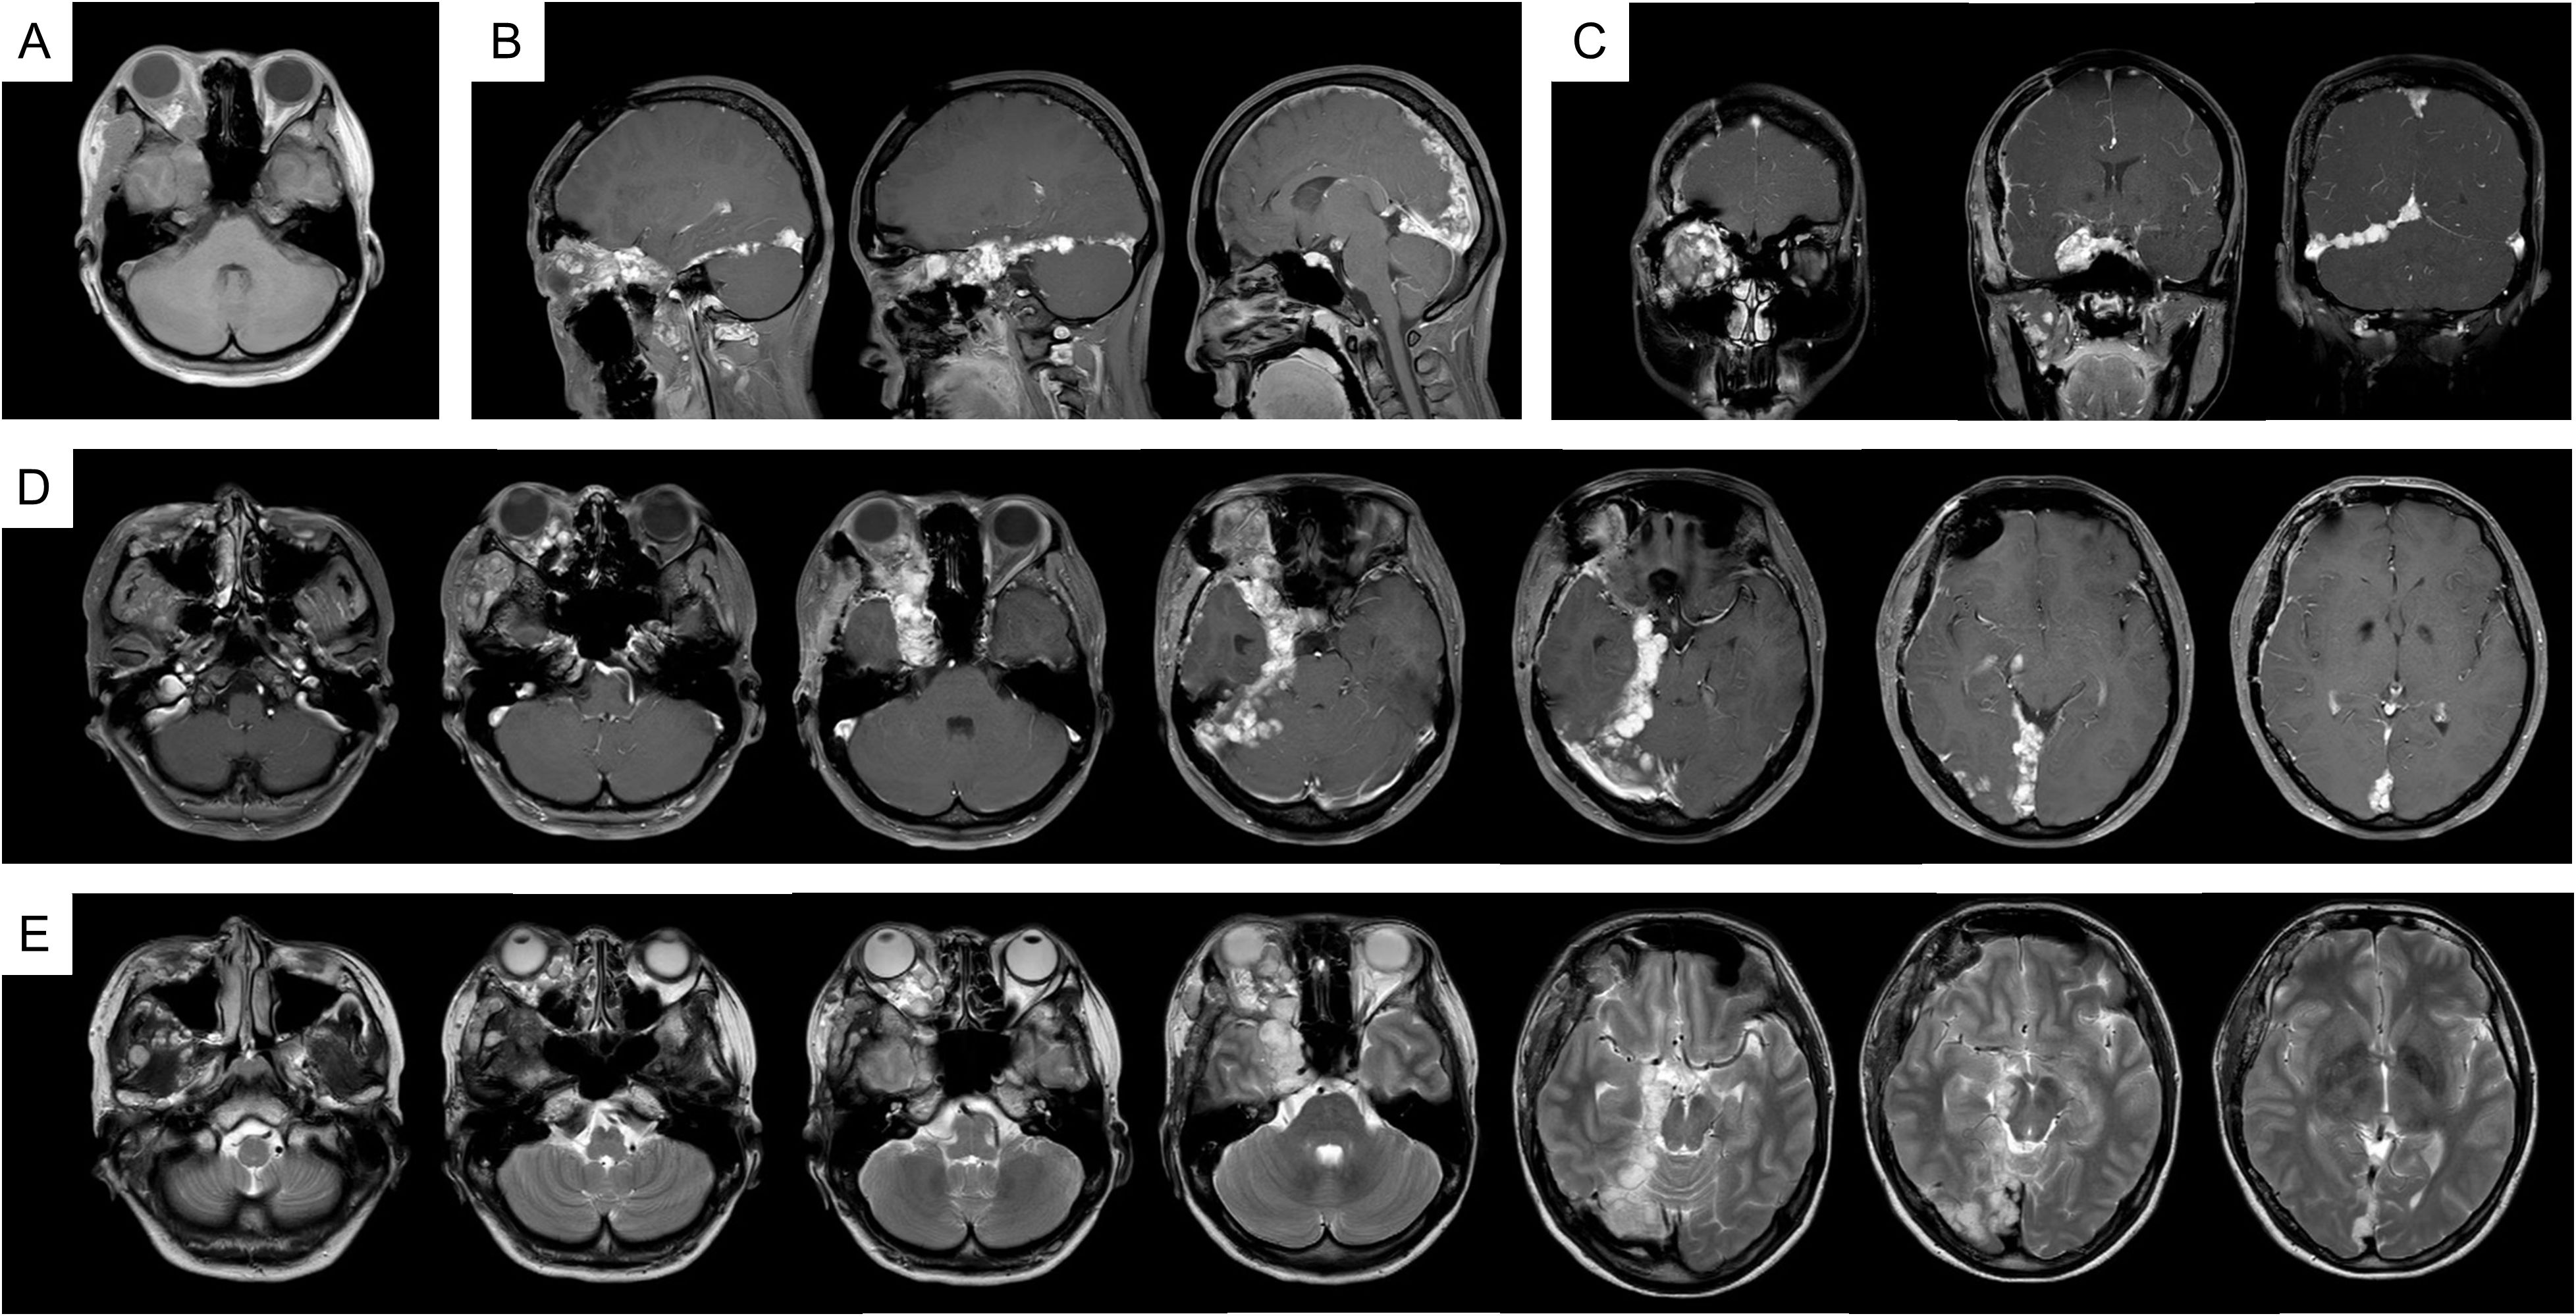

In 2023, due to worsening symptoms and brainstem compression (Figure 1), palliative surgical resection was performed. Multiple tumor nodules beneath the temporal muscle and intraorbital lesions were partially removed. Postoperative histopathological analysis confirmed the diagnosis of hemangioma, characterized by dilated vascular channels lined by a single layer of endothelial cells without atypia, consistent with a cavernous subtype. This pathological confirmation established the final diagnosis, thereby excluding other radiologically plausible differential diagnoses such as meningioma (which typically shows dural attachment and uniform enhancement), schwannoma (which often arises from cranial nerves with distinct borders), or arteriovenous malformation/hemangioblastoma (usually associated with flow voids or feeding vessels). At four months post-surgery, follow-up MRI (Figure 2) showed partial improvement of right cerebral edema, though a substantial intracranial tumor burden persisted.

Figure 2

Figure 2. MRI imaging after the palliative surgery. (A) T1WI; (B) T1WI-C coronal view; (C) T1WI-C sagittal view; (D) T1WI-C; (E) T2WI-TSE.